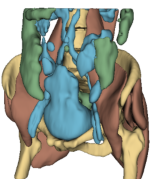

Fig. 2 presents a visual comparison of lung coronal sections from different models. The model using L1 loss results in blurred images, with particularly poor bone reconstruction. In contrast, the MedicalNet-based model produces sharper images but introduces artifacts in anatomical areas. Models based on AFP loss offer visually appealing results, with well-reconstructed anatomical bones and lung tissue. Additionally, only NaviAirway and HAL methods provide detailed bronchial reconstruction, as highlighted in the zoomed-in section.

To handle memory constraints during training and inference, we used a patch-based strategy. We experimented with multiple patch sizes, including and , and also used nnU-Net’s default adaptive windowing strategy (e.g. for thoracic cases). While larger patches provide more contextual information and generally improve reconstruction quality, the overall performance did not differ substantially from nnU-Net’s dynamic patching. Some visible artifacts in Fig.2 result from patch combination, especially in regions not covered by the segmentation network used for AFP supervision. For instance, when the AFP loss relies on the NaviAirway model, artifacts often appear outside the lung fields, as the network lacks anatomical guidance in those regions. However, these artifacts are purely visual and do not affect the downstream segmentation results or the quantitative metrics reported, which are detailed in the upcoming paragraph.

![]() |

| Real CT | L1 | Perceptual | AFP TotalSeg | AFP Navi | AFP Navi + HAL |

Table 1 presents a quantitative evaluation of the model’s performance on lung MR to CT synthesis, based on the MAE, SSIM, Dice score, and NSD between synthesized and ground truth CT images. The adapted nnU-Net trained with L1 loss delivers the best performance on intensity-based metrics, yielding a MAE of 48.72 and an SSIM of 0.837. In contrast, other models based on perceptual loss or AFP loss achieve average MAE results but maintain competitive SSIM values, for example, the AFP loss with TotalSegmentator embeddings achieves an SSIM of 0.828. In the context of airway segmentations using the NaviAirway pipeline, the adapted nnU-Net models with AFP loss from NaviAirway and HAL’s embeddings deliver the best performance, achieving the highest Dice score of 0.584 and NSD value of 0.723. Conversely, models employing L1, perceptual, or AFP loss with TotalSegmentator’s embeddings yield poorer results, lacking precise bronchial reconstruction. The GAN-based SPADE method generally underperforms compared to nnU-Net, but adding AFP loss to SPADE enhances its performance. These metrics align with qualitative analysis from Fig. 2 and Fig. 3, with the models using AFP loss delivering the best performance in airway reconstruction.